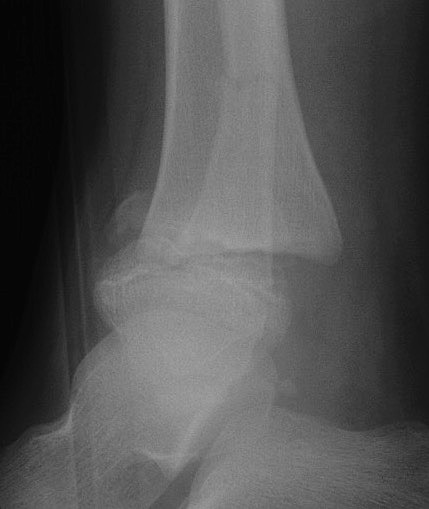

Triplanar Fracture

Definition

- fracture in coronal, sagittal and transverse planes

- 2, 3 or 4 part

Xray

Type III / Tillaux on AP

Type II on lateral

CT

Type III on coronal

Type II on sagittal

3 point star on axial

Management

ORIF

- > 2mm displacement

- usually anterolateral approach to reduce

- epiphyseal medial-lateral screw

- metaphyseal AP screw